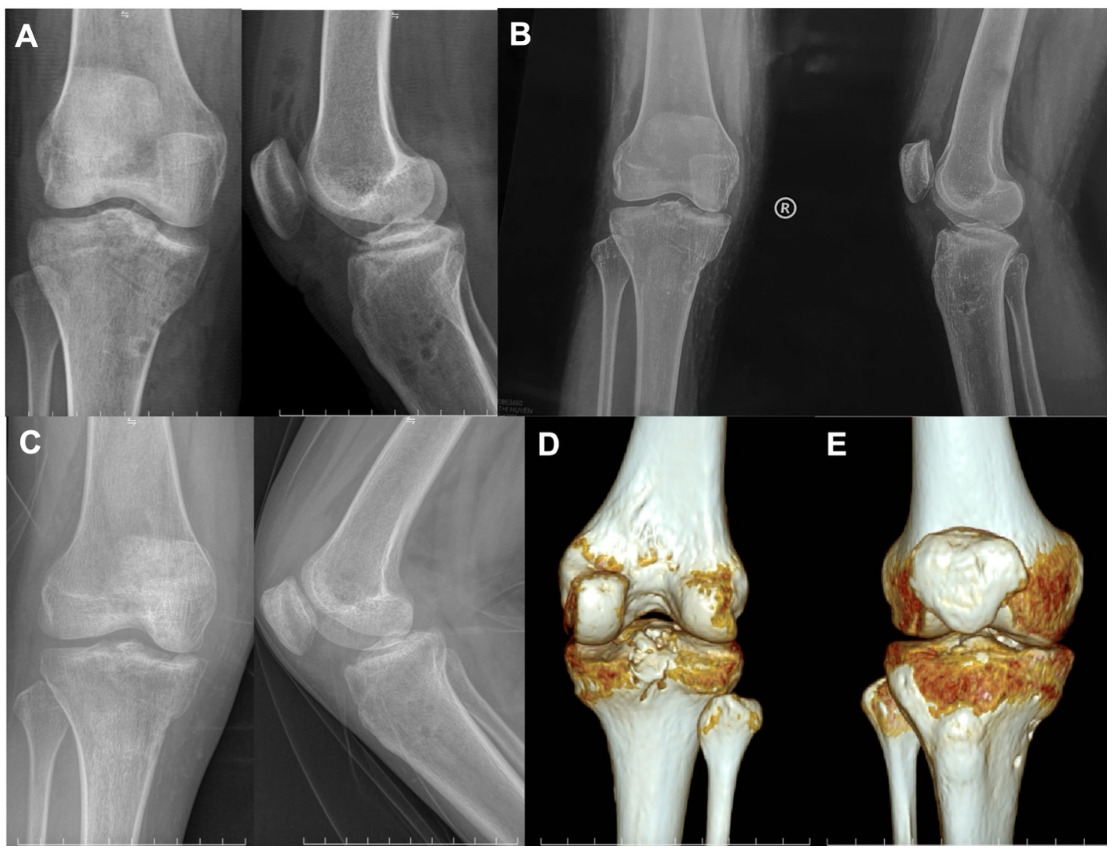

Immediate postoperative radiographs demonstrated anatomic reduction of the avulsed fragments (Fig 4A). Follow-up imaging at 1 month confirmed maintenance of stable fixation (Fig 4B). Radiographs and CT at 3 months revealed complete osseous union with preservation of anatomic alignment (Fig 4C, D, E). At 6 months postoperatively, the patient achieved a knee range of motion from 0° to 150°, with negative Lachman’s test and anterior–posterior drawer tests. Functional evaluation demonstrated an objective IKDC grade A, a subjective IKDC score of 100, and a Lysholm score of 100. The patient returned to normal daily activities without pain or residual instability.